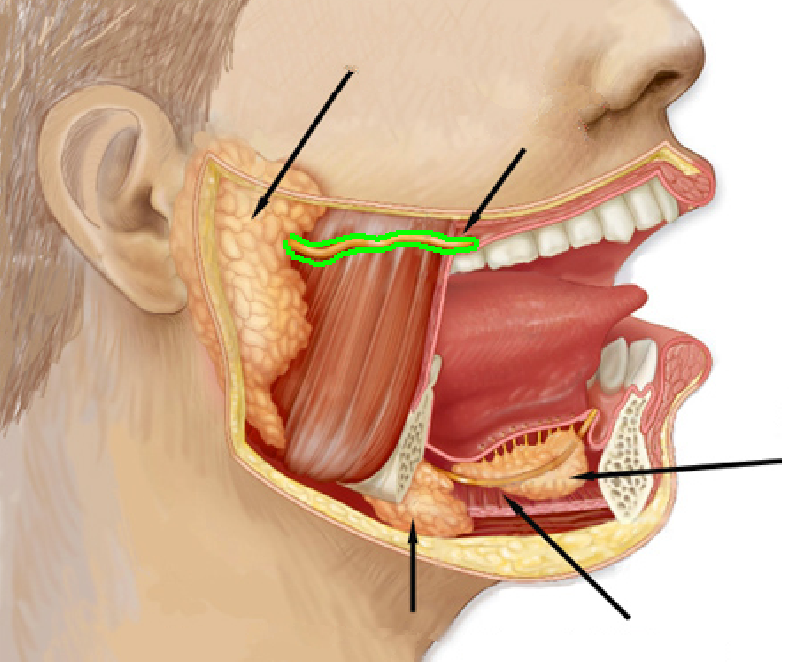

Parotid duct

Opening to parotid duct

Parotid gland